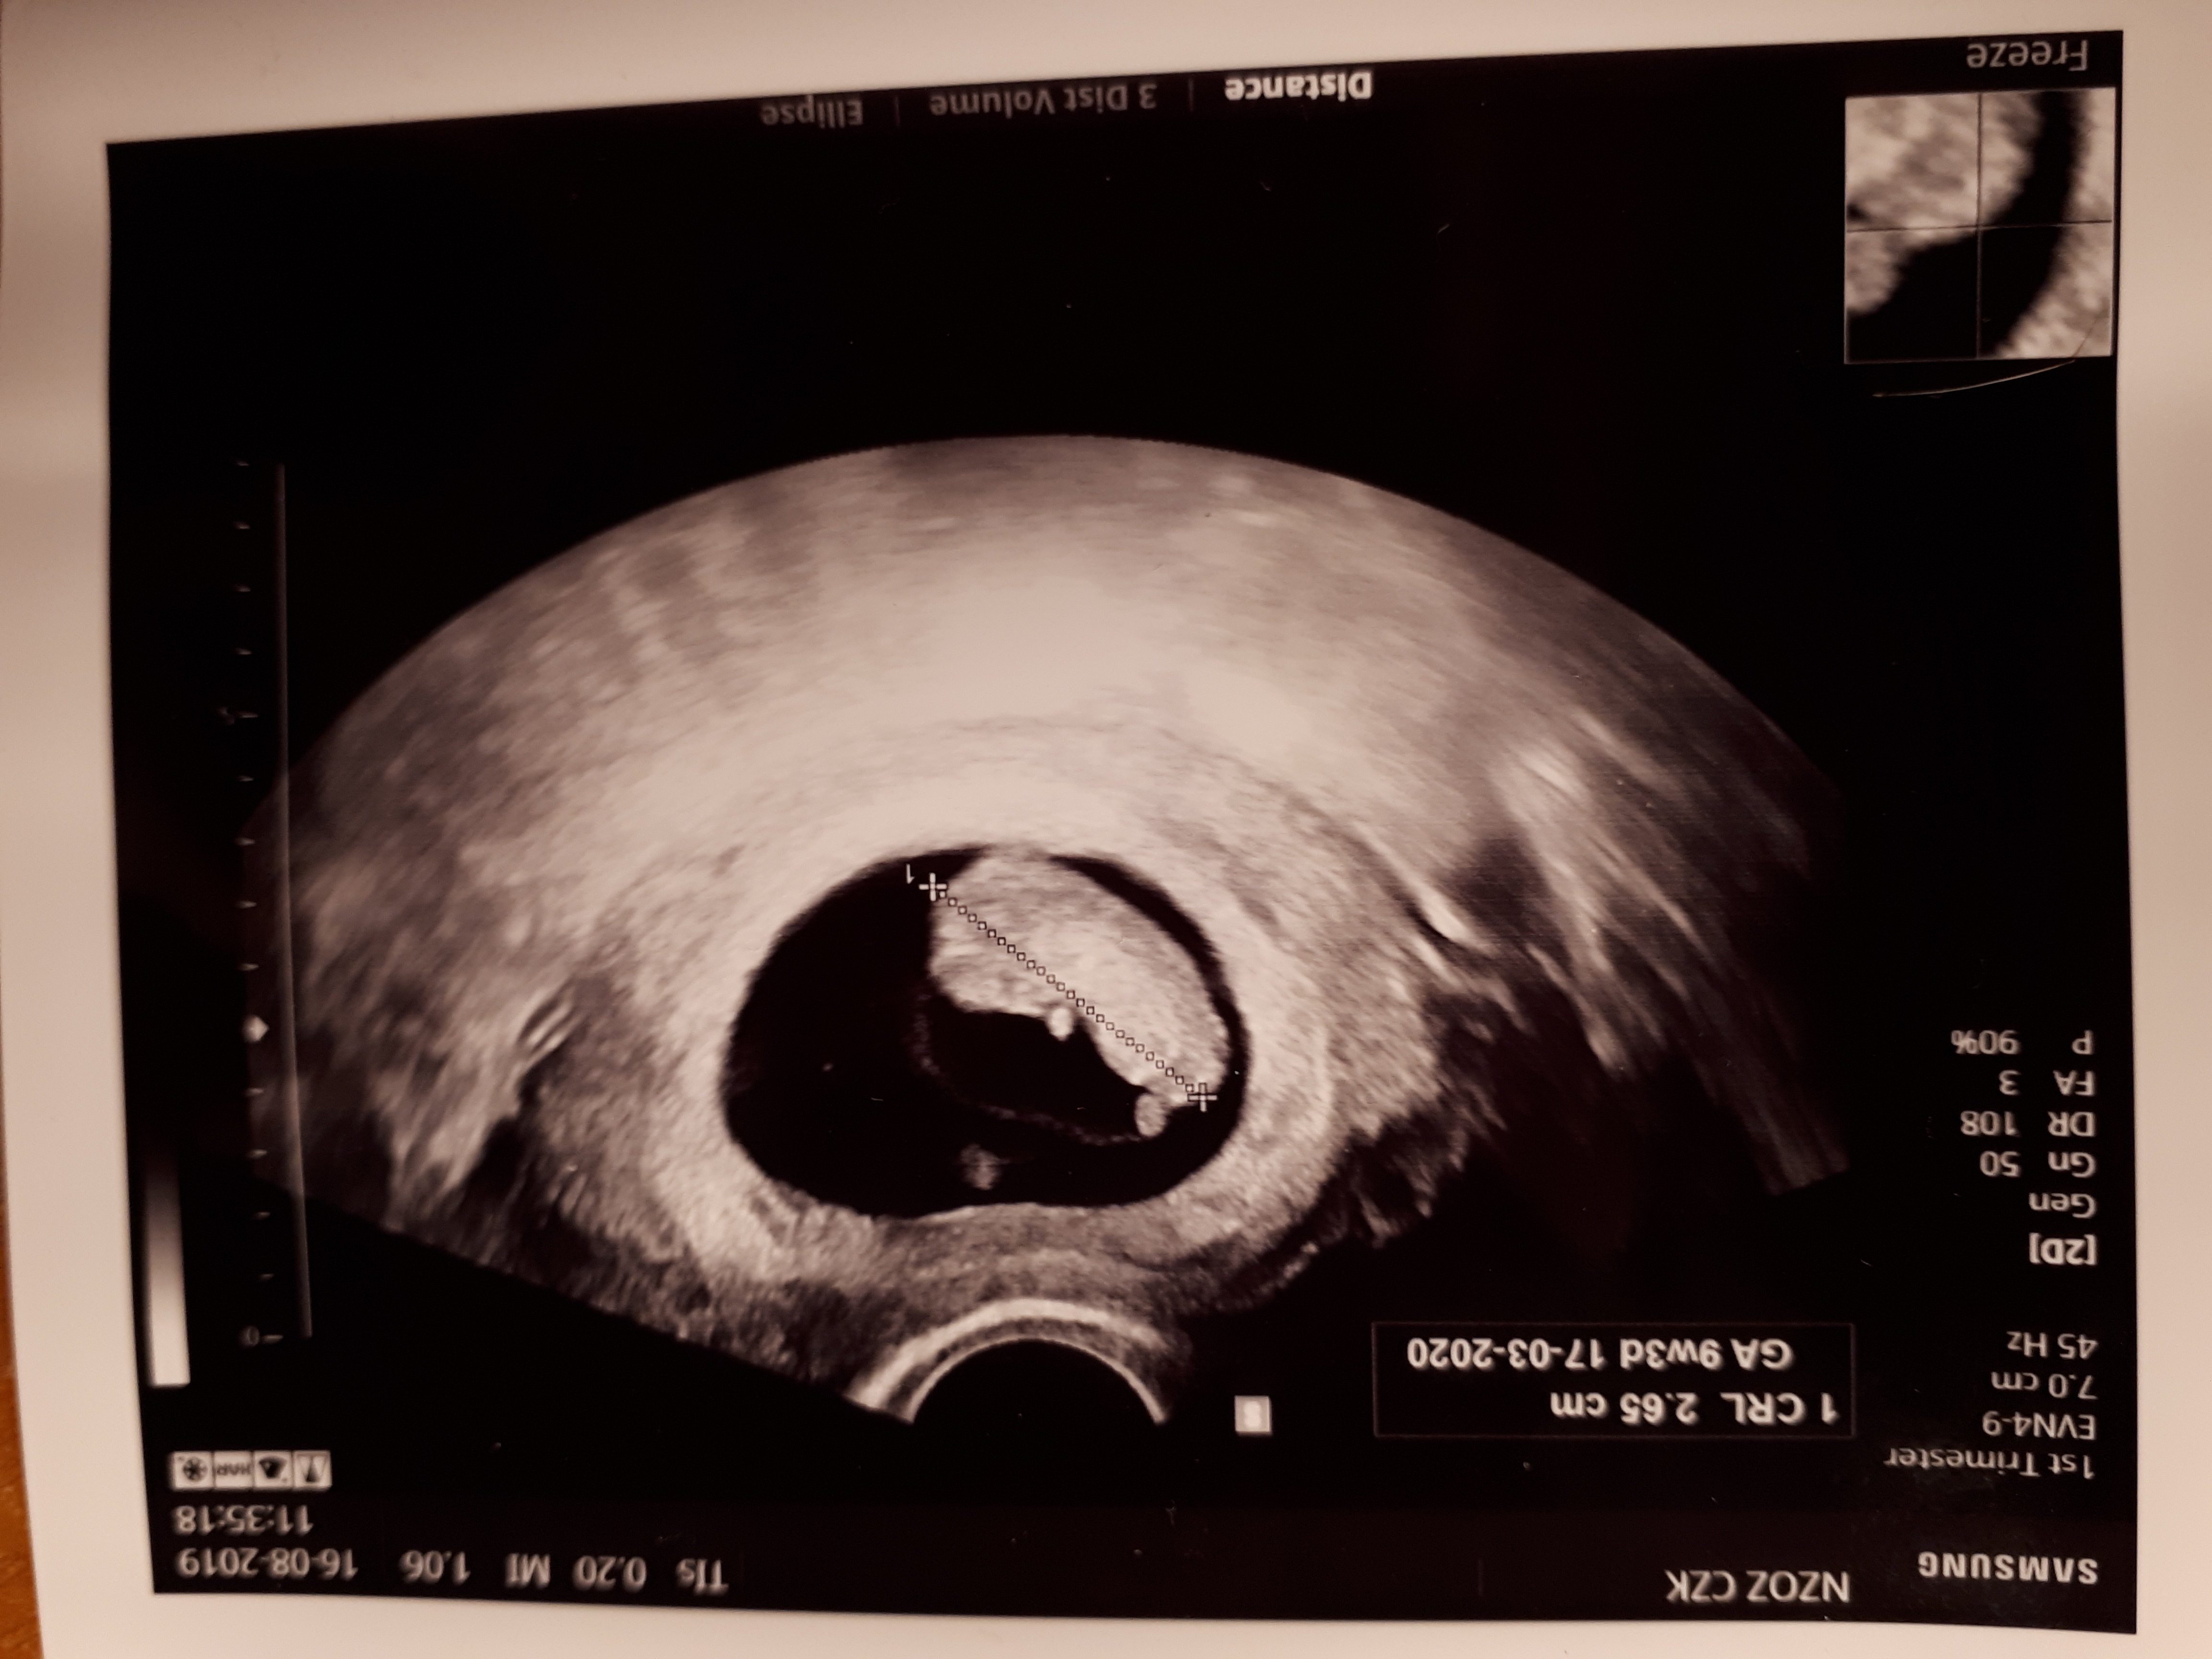

Dobra dziewczyny, zrobione USG genetyczne, wszystko jest w porzadeczku [emoji3590]

Całe badanie trwa właśnie koło 20 minut. Inaczej niż na dotychczasowych USG lekarz oglądał płód niemalże milimetr po milimetrze. Na szczęście dziecko było ruchliwe (specjalnie zjadłam wcześniej coś słodkiego żeby je pobudzić glukozą XD) więc poszło szybko znalezienie tego, co najważniejsze i mogliśmy z partnerem jeszcze sobie popatrzeć jak się rusza

To, co sprawdza lekarz - kość nosowa, przezierność karku (te rzeczy musi znaleźć i szuka do skutku), potem serce (tutaj podobno nie zawsze dobrze da się zobaczyć), pęcherz moczowy (tez było idealnie widać), w podczerwieni oglądał żyły i przepływ krwi, rączki, stopki, liczył paluszki. Wszystko jest w porządeczku.

Z takich rzeczy „ekstra” na które starczyło czasu: oglądaliśmy mózg, kręgosłup, ja z racji zawodu byłam ciekawa jak wyglada kręgosłup, miednica, dokładnie widać nawet kości - łokciową i promoeniową, piszczelową i strzałkową. Sprzęt był dużo dokładniejszy niż u mojego lekarza, poza tym były dwa ekrany, na jednym oglądał lekarz z partnerem, drugi był nad łóżkiem gdzie leżałam wiec widziałam dokładnie.

Na koniec jeszcze zrobił USG 3D (widać jak ssie palec [emoji23]) i dostaliśmy płytę CD z zapisem całego badania więc mogę sobie w domu odtworzyć film z tym co było na ekranie. Fajny gadżet, zwłaszcza ze nie wszystko widziałam bo mi się oczy zaszkliły [emoji23]

Cieszę się bardzo ze wszystko jest ok. A no i na 80% będzie dziewczynka, na moją prośbę lekarz podejrzał krocze (nie była zbyt wstydliwa [emoji23]) ale na tym etapie to jeszcze może costam „wyrosnąć”, dlatego 80%.